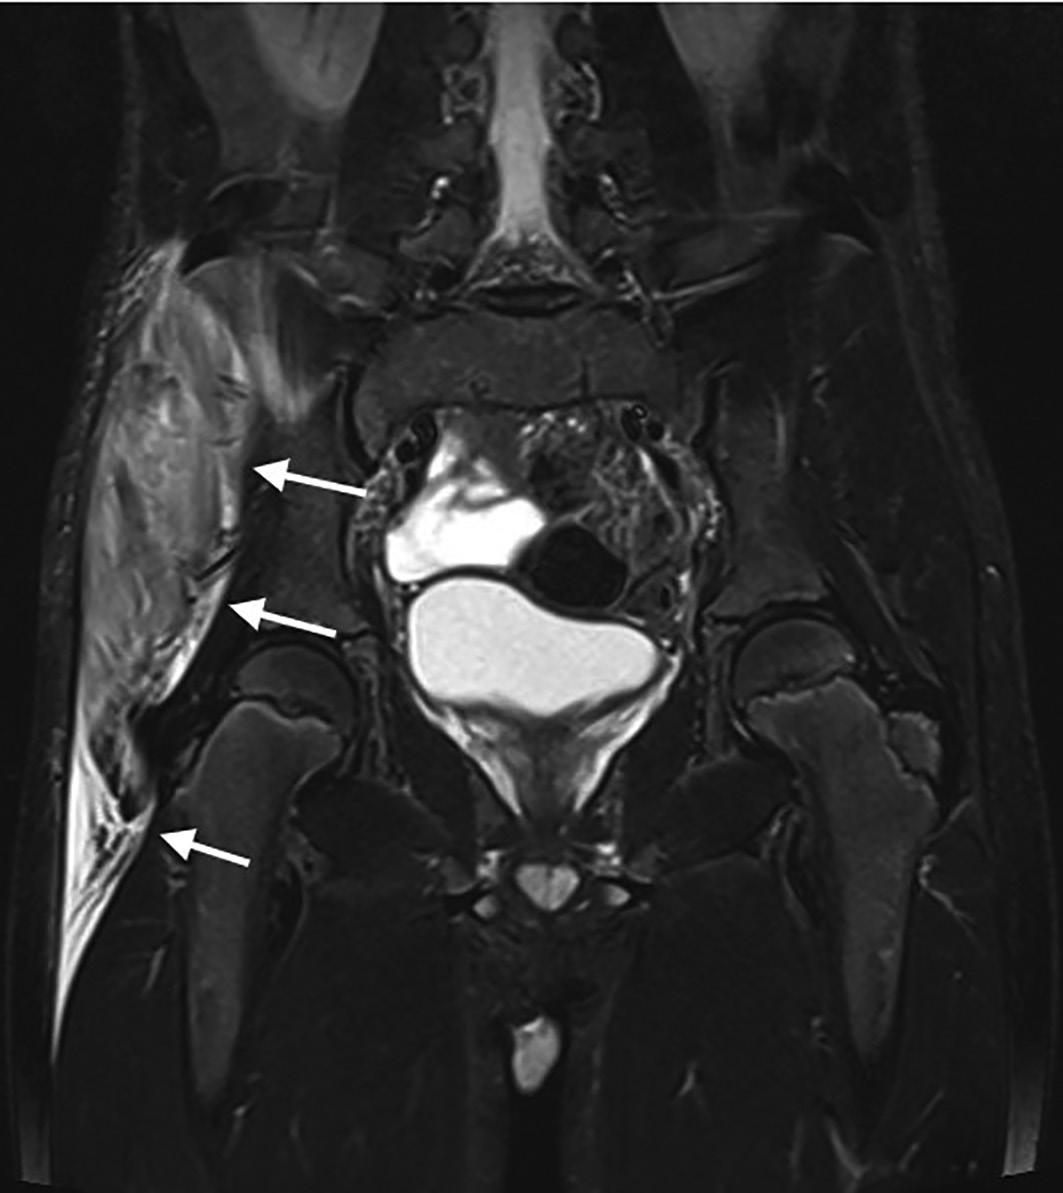

1 UO di Pediatria, Ospedale G.B. Morgagni – L. Pierantoni, AUSL della Romagna, Forlì; 2 Scuola di Specializzazione in Pediatria, Università degli Studi di Ferrara

La piomiosite – inizialmente conosciuta come patologia prevalentemente tropicale e oggi ben presente anche nelle zone temperate – è un’infezione suppurativa del muscolo scheletrico che può originare da un traumatismo o da un’intensa attività fisica che determina un danno della struttura muscolare. Spesso sostenuta da Staphylococcus aureus , entra in diagnosi differenziale con l’artrite settica, l’osteomielite e la cellulite. La descrizione di un caso osservato in un giovane atleta ci consente di ripercorrerne gli elementi diagnostici e terapeutici fondamentali.

Pyomyositis – initially known as a predominantly tropical disease and now well present also in temperate areas –is a suppurative infection of the skeletal muscle that can originate from trauma or intense physical activity that causes damage to the muscle structure. Often sustained by Staphylococcus aureus , it enters a differential diagnosis with septic arthritis, osteomyelitis and cellulitis. The description of a case observed in a young athlete allows us to retrace the fundamental diagnostic and therapeutic elements.

La storia di Sergio Sergio, ciclista dilettante di 11 anni, viene in pronto soccorso per la comparsa di dolore elettivo a livello della cresta iliaca di destra da circa quattro giorni, associato a zoppia e febbre (TC max 38,5 °C) da un giorno, scarsamente responsiva agli anti piretici. Riferisce inoltre alcuni episodi di vomito alimenta re. Non riporta di avere subito traumi significativi. Il ragazzo è, complessivamente, in buone condizioni generali e a carico dell’articolazione coxo-femorale di destra non ci sono segni di infiammazione locale né limitazione ai movimenti di intra- ed extrarotazione. Lamenta dolore solo alla digitopressione del la regione antero-superiore della cresta iliaca di destra. La re stante obiettività è nei limiti della norma. Tra gli esami, emo cromo, funzionalità epatica e renale sono nella norma con un incremento della PCR (58,1 mg/L) e negatività della sierolo gia per parvovirus B19, CMV, EBV, micoplasma, bartonella e Widal-Wright. Anche la radiografia del bacino non evidenzia lesioni ossee.

Nell’ipotesi di un’osteomielite acuta si avvia trattamento con oxacillina per via endovenosa. Dopo 72 ore di terapia antibio tica, persistendo la febbre e pervenuta la positività dell’emo coltura per Staphylococcus aureus multisensibile, si sostitui sce la terapia in atto con la clindamicina per via endovenosa. In quarta giornata di ricovero la RM del bacino mostra estesi fenomeni di infiltrazione edematoso-flogistica con alcuni fo colai ascessuali che interessano soprattutto il muscolo medio gluteo e in minor misura l’ala iliaca destra [Figura 1]. Il qua dro è complessivamente suggestivo di piomiosite con inizia le coinvolgimento del periostio e dell’osso. Durante la degen

Figura 1. RM all’esordio che mostra l’interessamento infiammatorio del muscolo medio gluteo e dell’ala iliaca destra.

za Sergio migliora progressivamente riuscendo a deambulare seppure con gli ausili e resta apiretico dalla sesta giornata di trattamento. Dopo 16 giorni complessivi di terapia antibiotica endovenosa, gli esami mostrano la completa negatività degli indici di flogosi, l’ecografia muscolare rileva un’apprezzabile riduzione dell’area di infarcimento edematoso-flogistico sen za più evidenza dei focolai ascessuali. Il ragazzo viene dimesso con indicazione a proseguire la terapia con clindamicina per via orale per un totale di 21 gg. La RM, eseguita a distanza di un mese dalla precedente, documenta un significativo miglio ramento del quadro flogistico-suppurativo a carico del mu scolo medio gluteo, rimanendo solo una circoscritta area di interessamento nelle porzioni più craniali in adiacenza dell’a la iliaca. La terapia antibiotica viene proseguita per altre tre settimane e l’ulteriore RM a due mesi dall’esordio conferma la pressoché totale risoluzione dell’interessamento muscolare e osseo [Figura 2].

Quello che c’è da sapere sulla piomiosite (PM) Inizialmente descritta, alla fine dell’Ottocento, come miosite tropicale perché particolarmente frequente (1-4% dei ricove ri ospedalieri) nelle regioni tropicali subsahariane e in Brasi le, Giappone e Uganda, la PM è una patologia che colpisce più frequentemente adolescenti e giovani adulti anche se può in sorgere in tutte le fasce di età, con una maggiore incidenza nel sesso maschile. La sua crescente diffusione, anche nelle regio